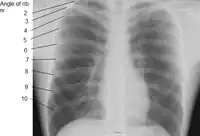

Additional images

X-ray image of a human chest, with ribs labelled